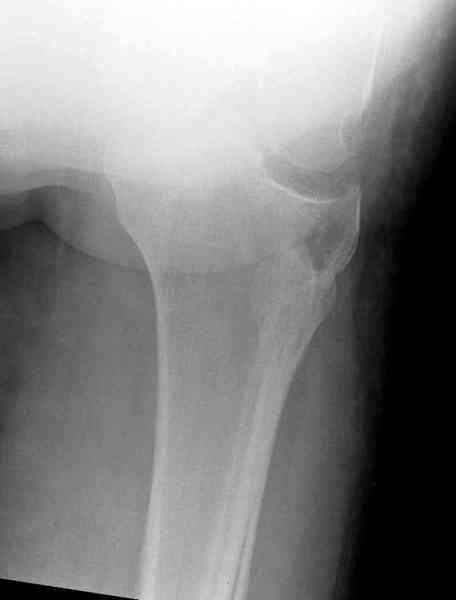

Из медиального окна можно приподнять латеральную

импрессию. Фиксация тремя параллельными шурупами в

эпифизарной части над импрессией. Создается крыша,

которая предупредит коллапс. На образовавшуюся полость - костная пластика из аутокости или синтетический заменитель. Мы применяем Osteoset в 4-5 мм диаметре таблеточки или иньекционную форму Prodens.